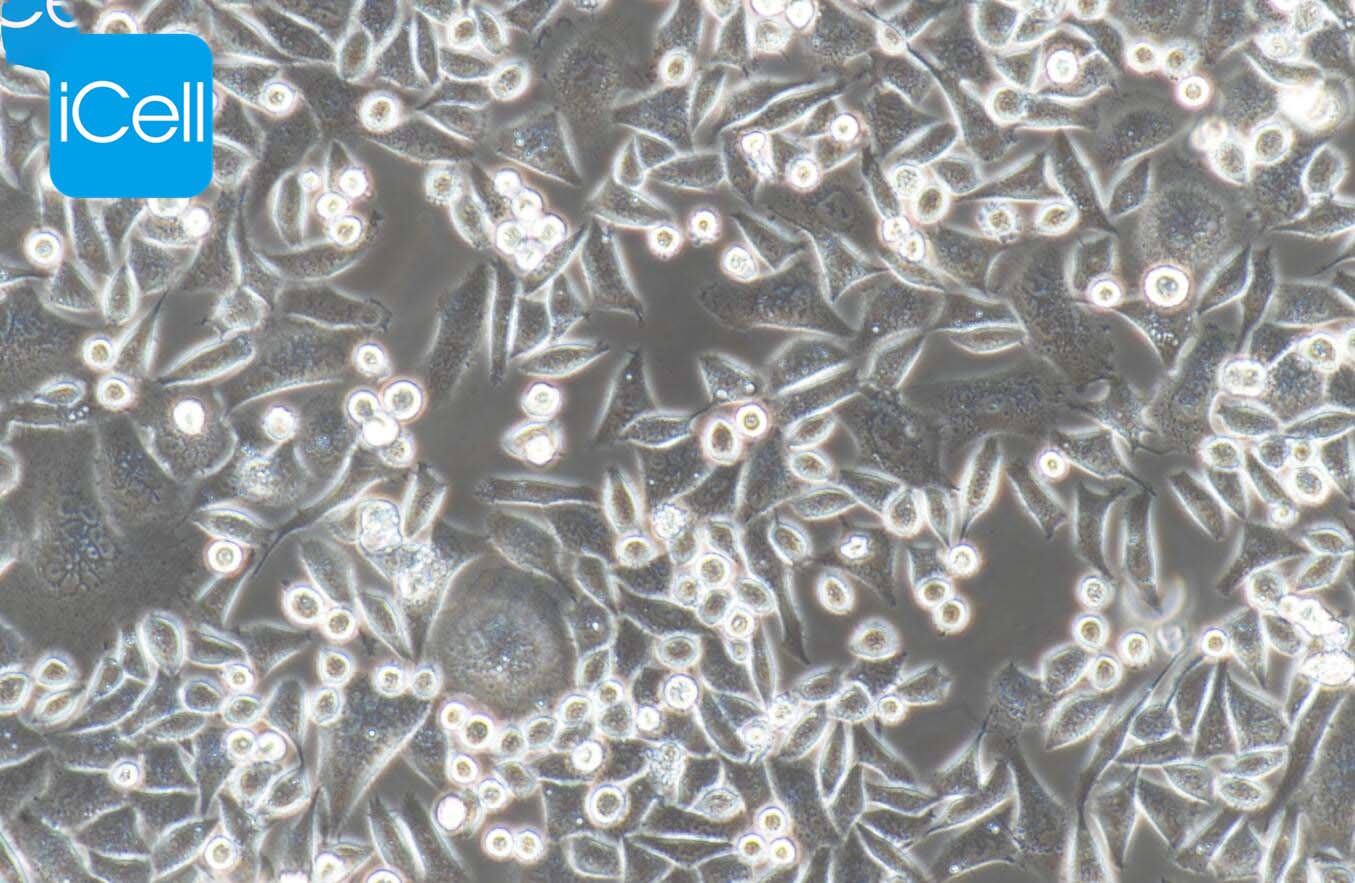

上皮细胞样

细胞介绍

BEL-7402细胞株是1974年从临床肝癌手术标本中建立的。 细胞群体倍增时间为20小时。移植到处理过的wistar大鼠中的能形成肿瘤结节。细胞形态呈上皮样细胞。在电子显微镜下亦显示上皮细胞所具有的桥粒和张力原纤维,与临床肝癌细胞相似。分瓶培养第四天时,其有丝分裂指数约为7%。 BEL-7402细胞的染色体数为不足三倍体,有一个异常的近端着丝点染色体。间接免疫荧光法测BEL-7402细胞内的AFP为阳性反应。LDH同工酶谱显示与成年人肝细胞不同,而与人胚肝及临床肝癌相近。

2) 形态:上皮细胞样,贴壁生长